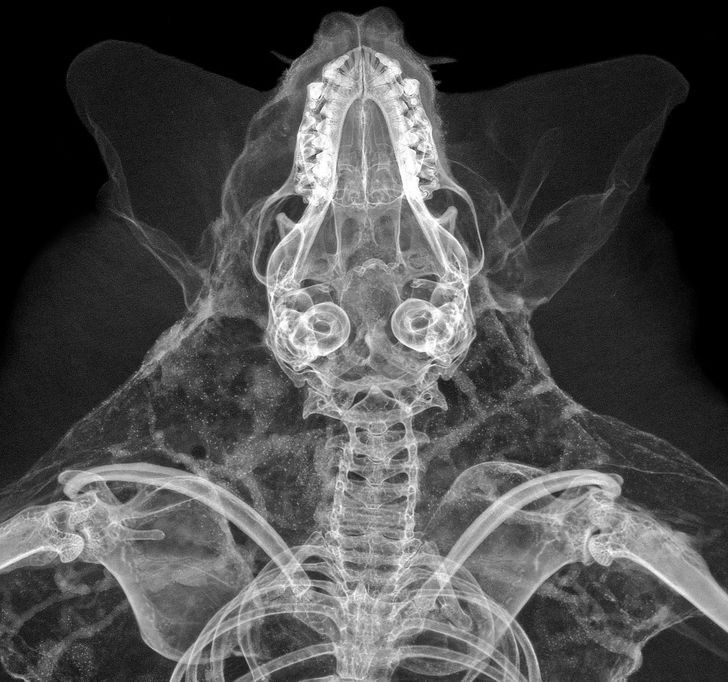

Этот снимок летучей мыши просто пятно Роршаха какое-то — можно вглядываться бесконечно